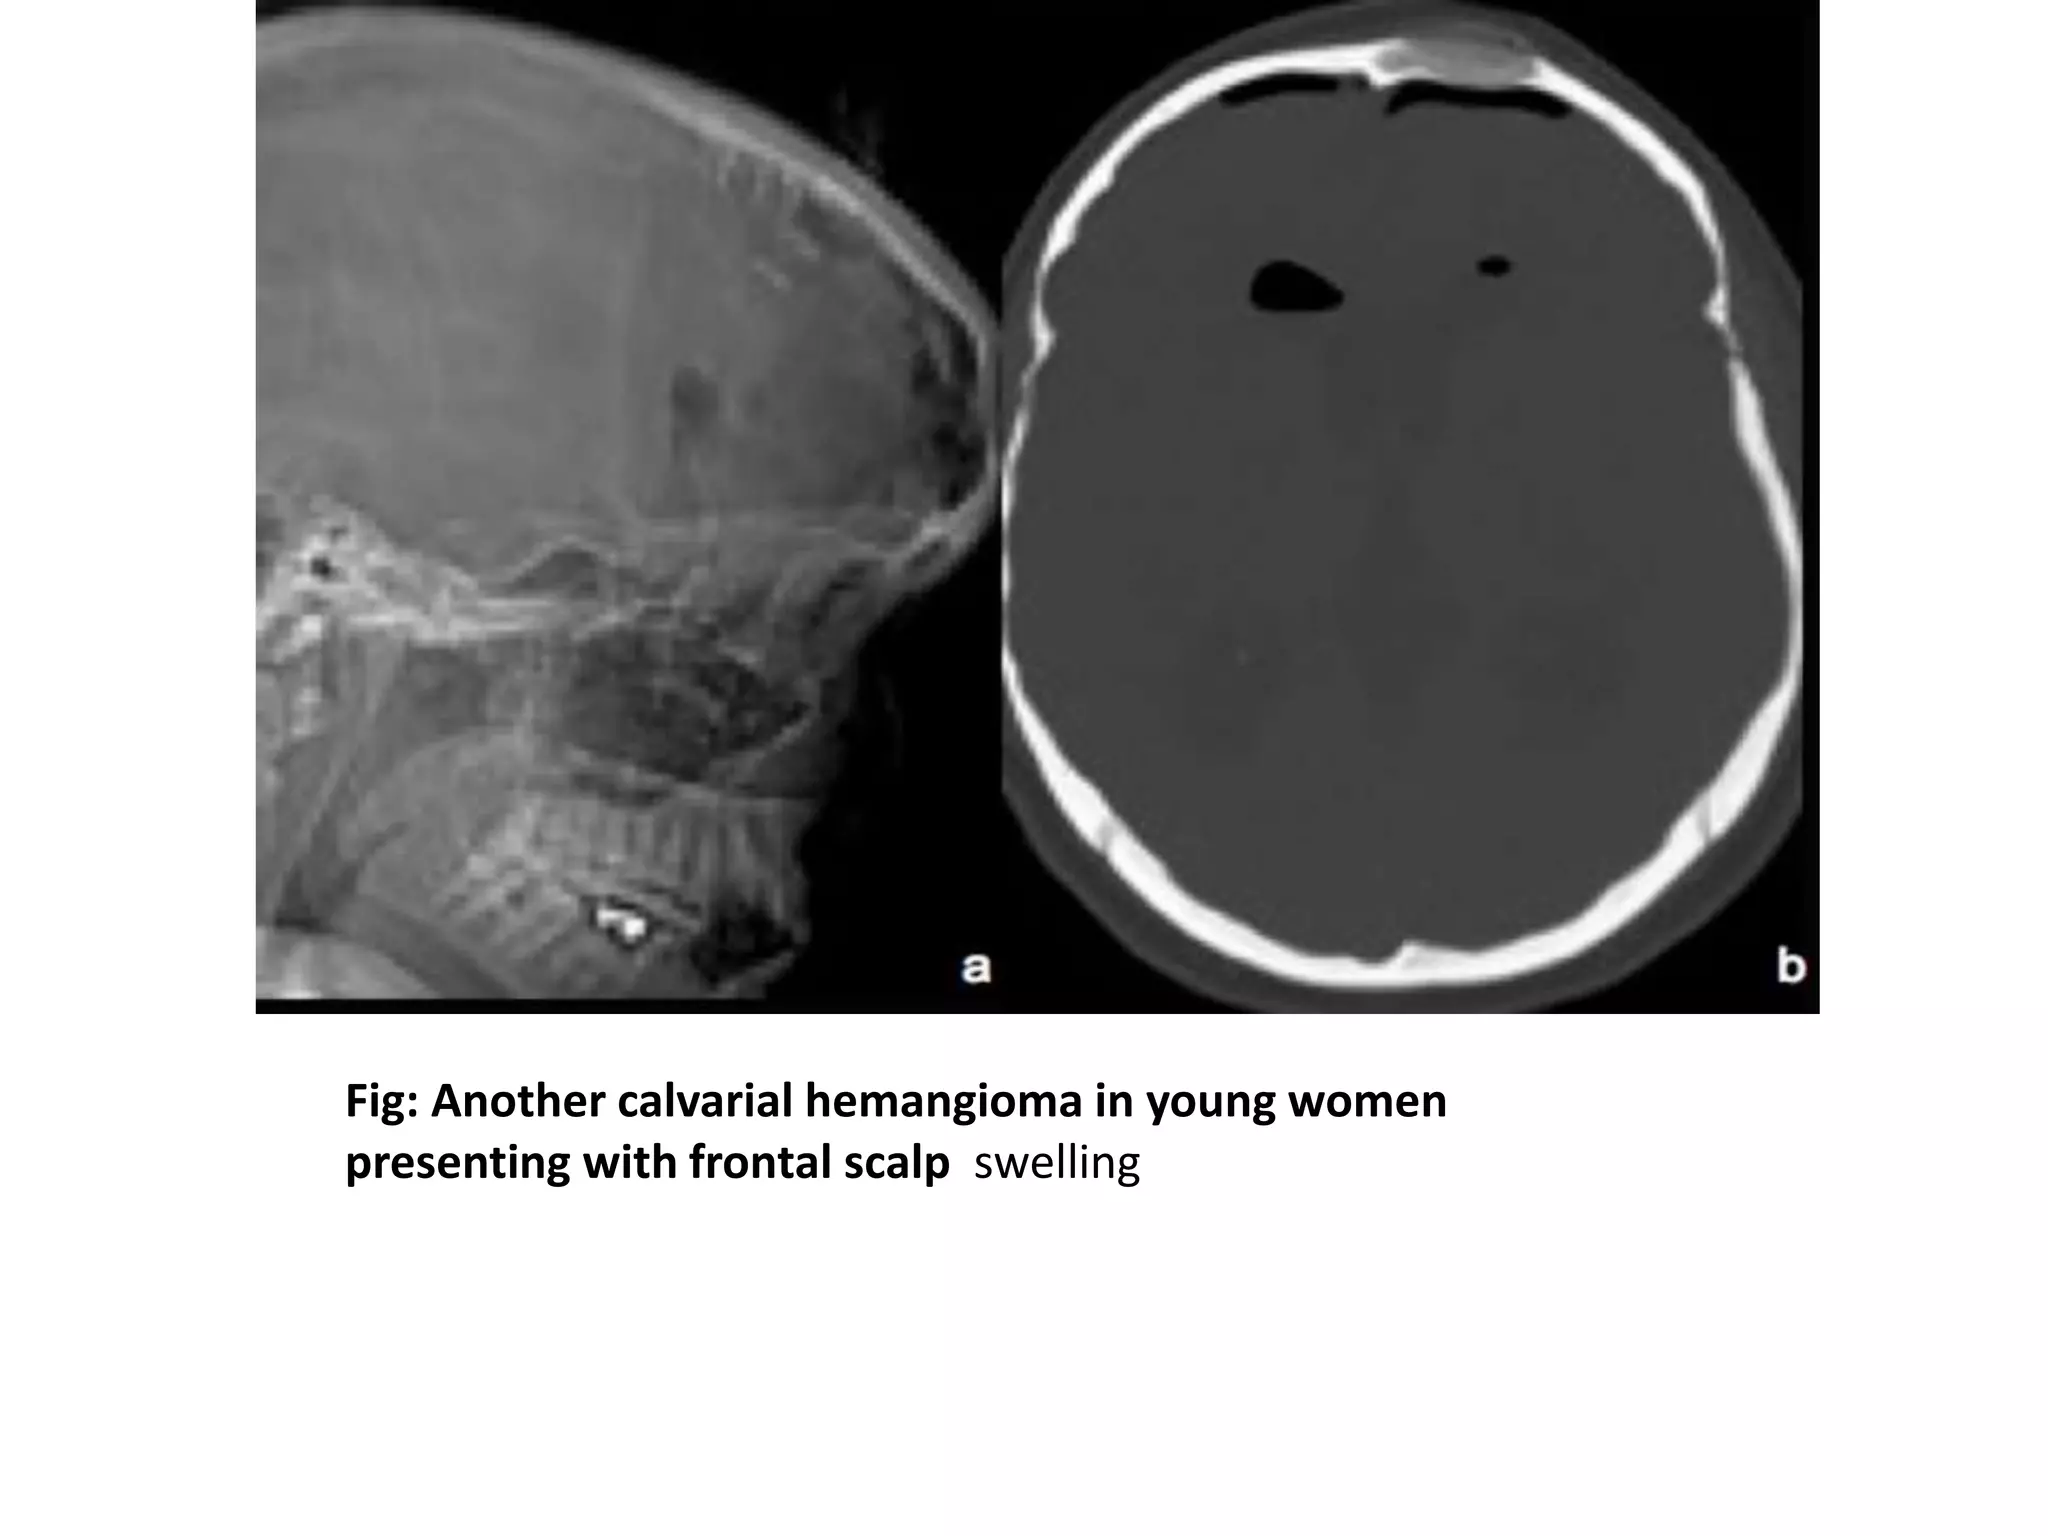

Fig: Another calvarial hemangioma in young women

presenting with frontal scalp swelling

Fig: Another calvarialhemangioma in young women presenting with frontal scalp swelling